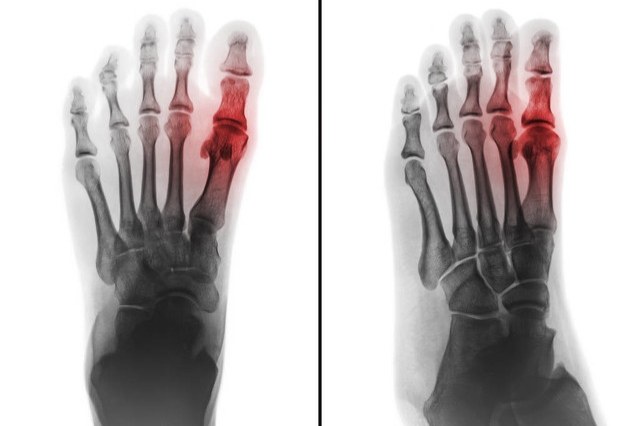

首先我们先了解一下痛风,痛风是因嘌呤代谢障碍引起的代谢性疾病,当血中尿酸浓度过高和(或)在酸性环境下,尿酸可析出结晶,沉积在关节内,引起痛风性关节炎。

痛风急性发作是因尿酸代谢异常诱发的局部无菌性炎症反应,与细菌感染无关,所以 吃头孢类、青霉素类等“消炎药”不会有作用!